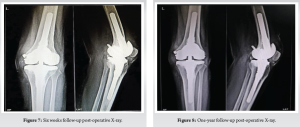

The patient was considered for conventional TKA. The previous surgical scar for debridement through a midline incision followed by a medial parapatellar approach was used for the surgery. Using a legacy constrained condylar knee jig, distal femur and proximal tibia cuts were made. Size D femur was prepared with sequential rimming of the medullary canal of both the tibia and femur for stem placement. An intramedullary extension stem of size 12 mm by 100 mm was fixed with size D cemented femur and tibia size two with 11-mm by 100-mm extension stem, cemented with a 10-mm insert. The osteoporotic medial femoral condyle was supported with a 6-mm cannulated cancellous crew. Final implant placement was followed by thorough washing and closure in layers. Postoperatively, the patient was permitted to bear weight as tolerated, and the knee was immobilized in extension for 2 weeks. Thereafter, passive knee flexion was advanced gradually. Active knee extension with activity as tolerated was permitted after 6 weeks. One year later, the patient remained free of systemic and local infection and had a well-functioning prosthesis without any loosening. The range of motion was 0–100° with no extensor lag. Radiographs of 6 months and 1 year follow-up (Fig. 7 and 8) confirmed a well-fixed and well-positioned stemmed prosthesis with no evidence of bone destruction.

During the first 6 months follow-up, the patient showed elevated serum inflammatory markers but no clinical signs. This was managed by monitoring, and subsequently, the markers normalized after 6 months without any clinical signs of inflammation. There was no relapse of symptoms such as swelling, redness, or abscess formation in the following year. Follow-up X-rays did not show any loosening of the prosthesis, and the patient was walking comfortably without any walking aids.